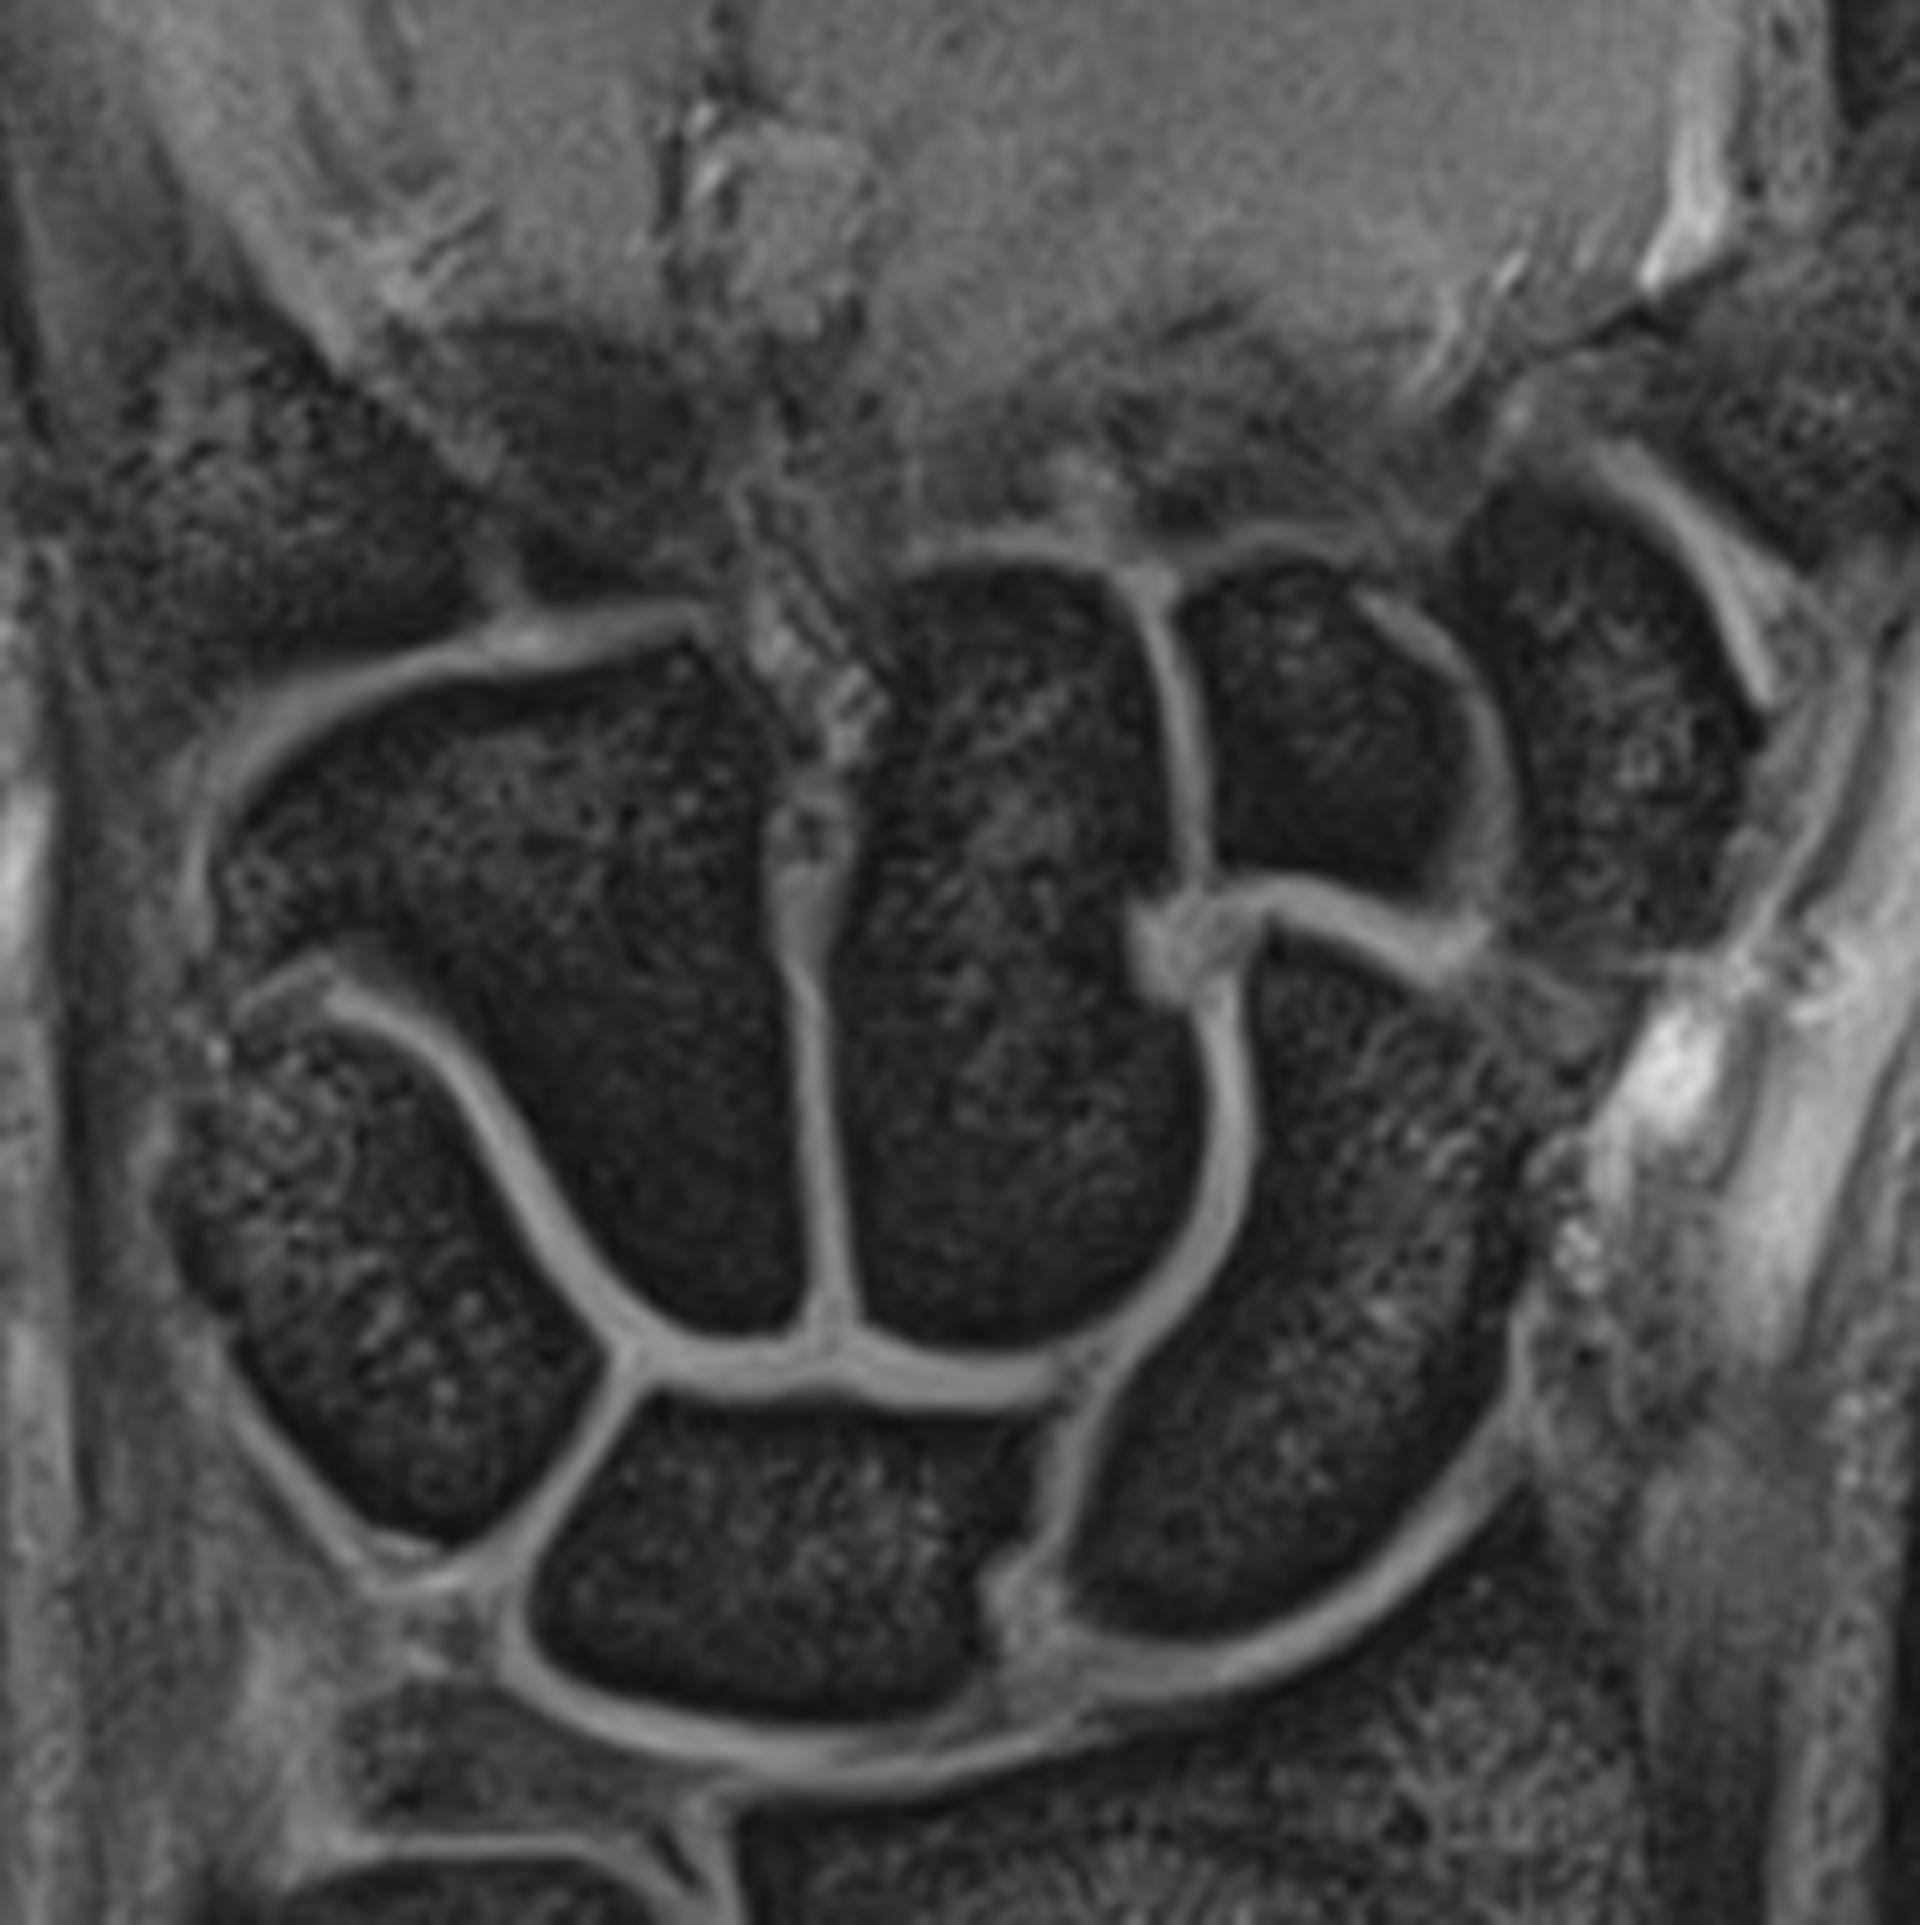

Discover how an MRI wrist joint scan provides detailed imaging to accurately diagnose complex injuries, ligament tears, and chronic pain. Learn why this advanced medical imaging procedure is essential for identifying bone, tendon, and soft tissue conditions, helping your doctor create an effective treatment plan for improved wrist health and faster recovery.

Read full article: Mri Wrist Joint